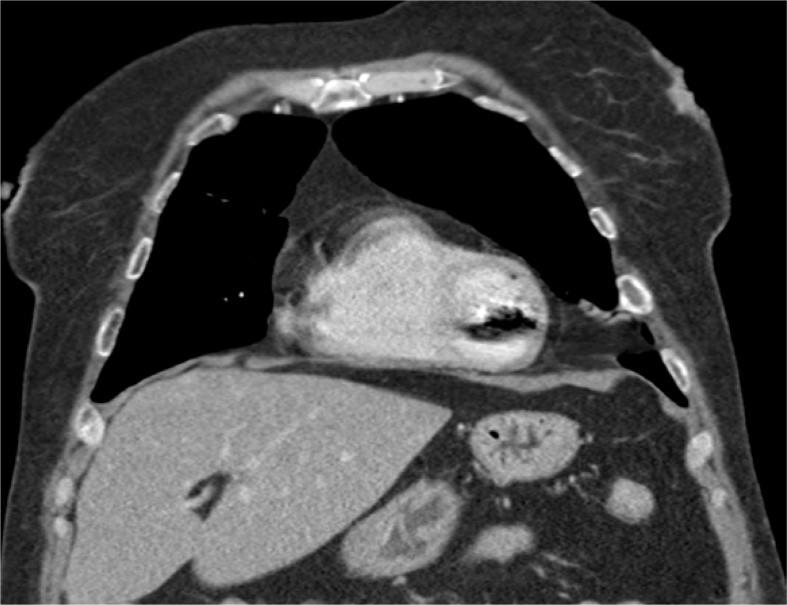

Fig. 1.

Systemic air found within the left ventricle.

Fig. 2.

Air embolism in left ventricle.

A 60-year-old female presented for an elective CT guided percutaneous lung biopsy of an incidentally found pulmonary nodule. The procedure was performed under moderate sedation with the patient in the prone position for biopsy planning and lesion selection, as the patient had multiple bilateral lower lobe masses. Three core biopsies were obtained from a left lower lobe lesion using a 19g introducer needle and a 20g biopsy gun. Following completion of the proceedings, the patient experienced a syncopal episode with decreased responsiveness despite sternal rub. The patient remained hemodynamically stable, with unchanged oxygen saturation remaining at 100% on 2L nasal cannula. A repeat chest CT was performed for concern over an iatrogenic pneumothorax. Instead, free air was demonstrated within the left ventricle and only a small pneumothorax in the vicinity of the biopsy site. A stat echo was performed at the bedside to assess for large PFO to determine etiology of air embolus and presence of residual intracardiac air. No PFO was identified to suggest right to left shunt as etiology for air embolism and no intracardiac air was seen (see Fig. 1, Fig. 2, Fig. 3).